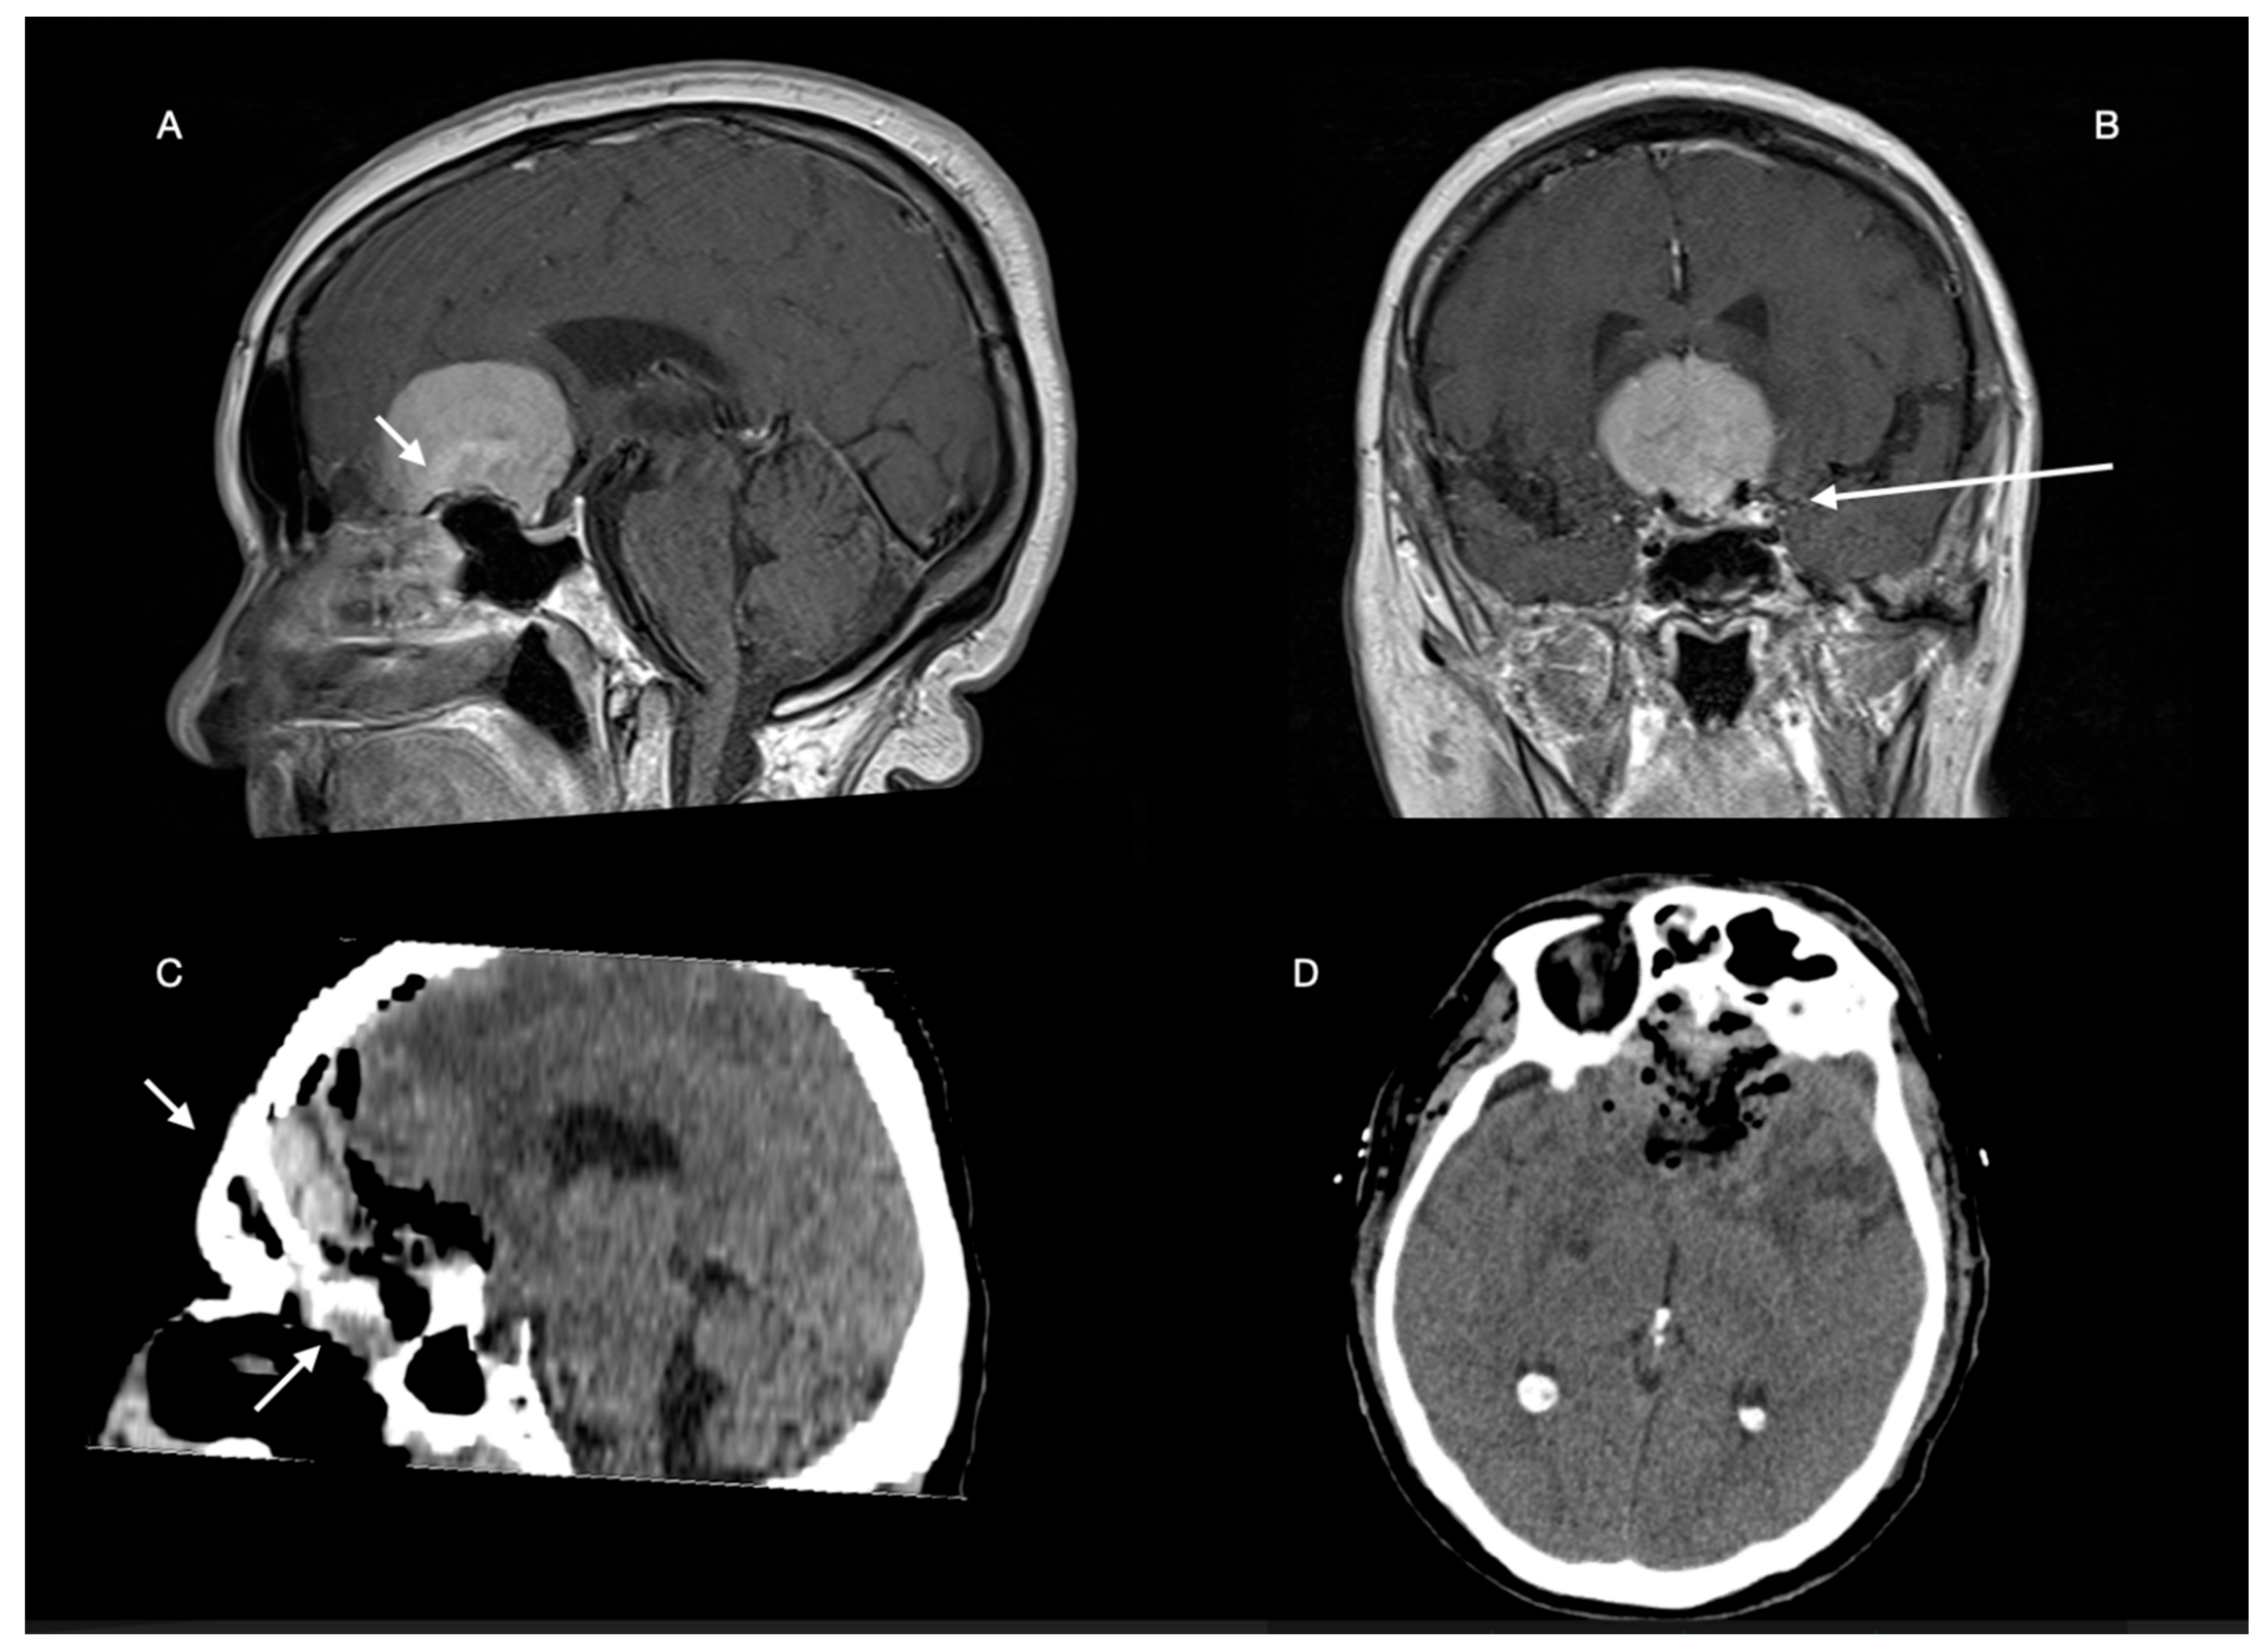

- Tumors classified as giant meningiomas (Group A): The contrast-enhanced lesion measured at least 5 cm along the major diameter in T1-weighted images with MRI;

- tumors classified as medium/large meningiomas (Group B): The contrast-enhanced lesion measured less than 5 cm along the major diameter in T1-weighted images with MRI.